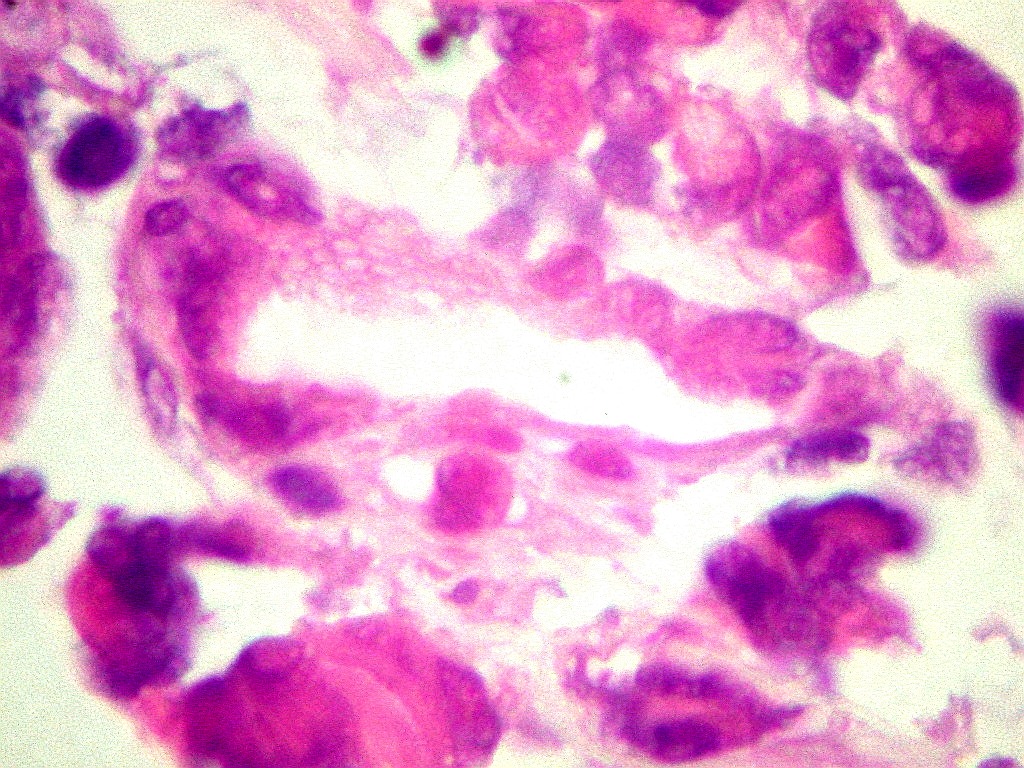

Destaca

núcleo excêntrico, deslocado pelo corpúsculo rabdóide. |